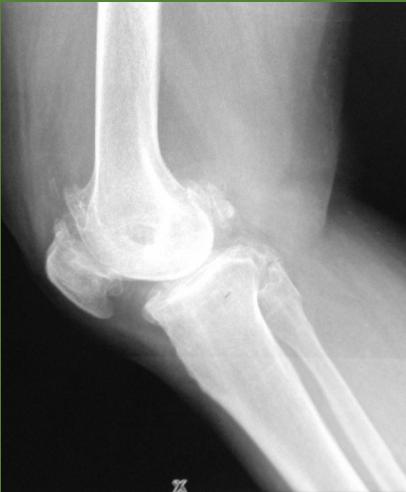

Hip osteoarthritis comparison images: * Hip without Osteoarthritis (for comparison)